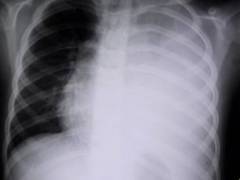

Рентгенологическое обследование — один из наиболее информативных методов, позволяющий выявить признаки воспаления и количество жидкости в плевральной полости.

Признаки при сухом плеврите на рентгене:

- купол диафрагмы с пораженной стороны выше нормы;

- снижение прозрачности легочной ткани.

Признаки при выпотном плеврите:

- сглаживание диафрагмального угла;

- однородное затемнение нижней области легочного поля;

- смещение средостения в сторону здорового легкого.

Рентгенологическое исследование — информативный метод диагностики плеврита, позволяющий выявить воспалительные процессы в плевре и оценить объем жидкости в плевральной полости. Рентгенография легких также помогает обнаружить заболевания, способствующие развитию плеврита, такие как пневмония, туберкулез и опухоли.

При сухом плеврите на рентгеновских снимках наблюдаются:

- купол диафрагмы с пораженной стороны выше обычного уровня;

- снижение прозрачности легочной ткани из-за воспаления серозной оболочки.

При выпотном плеврите фиксируются следующие рентгенологические признаки:

- сглаживание угла диафрагмы из-за накопления жидкости;

- однородное затемнение в нижней части легочного поля с наклонной границей;